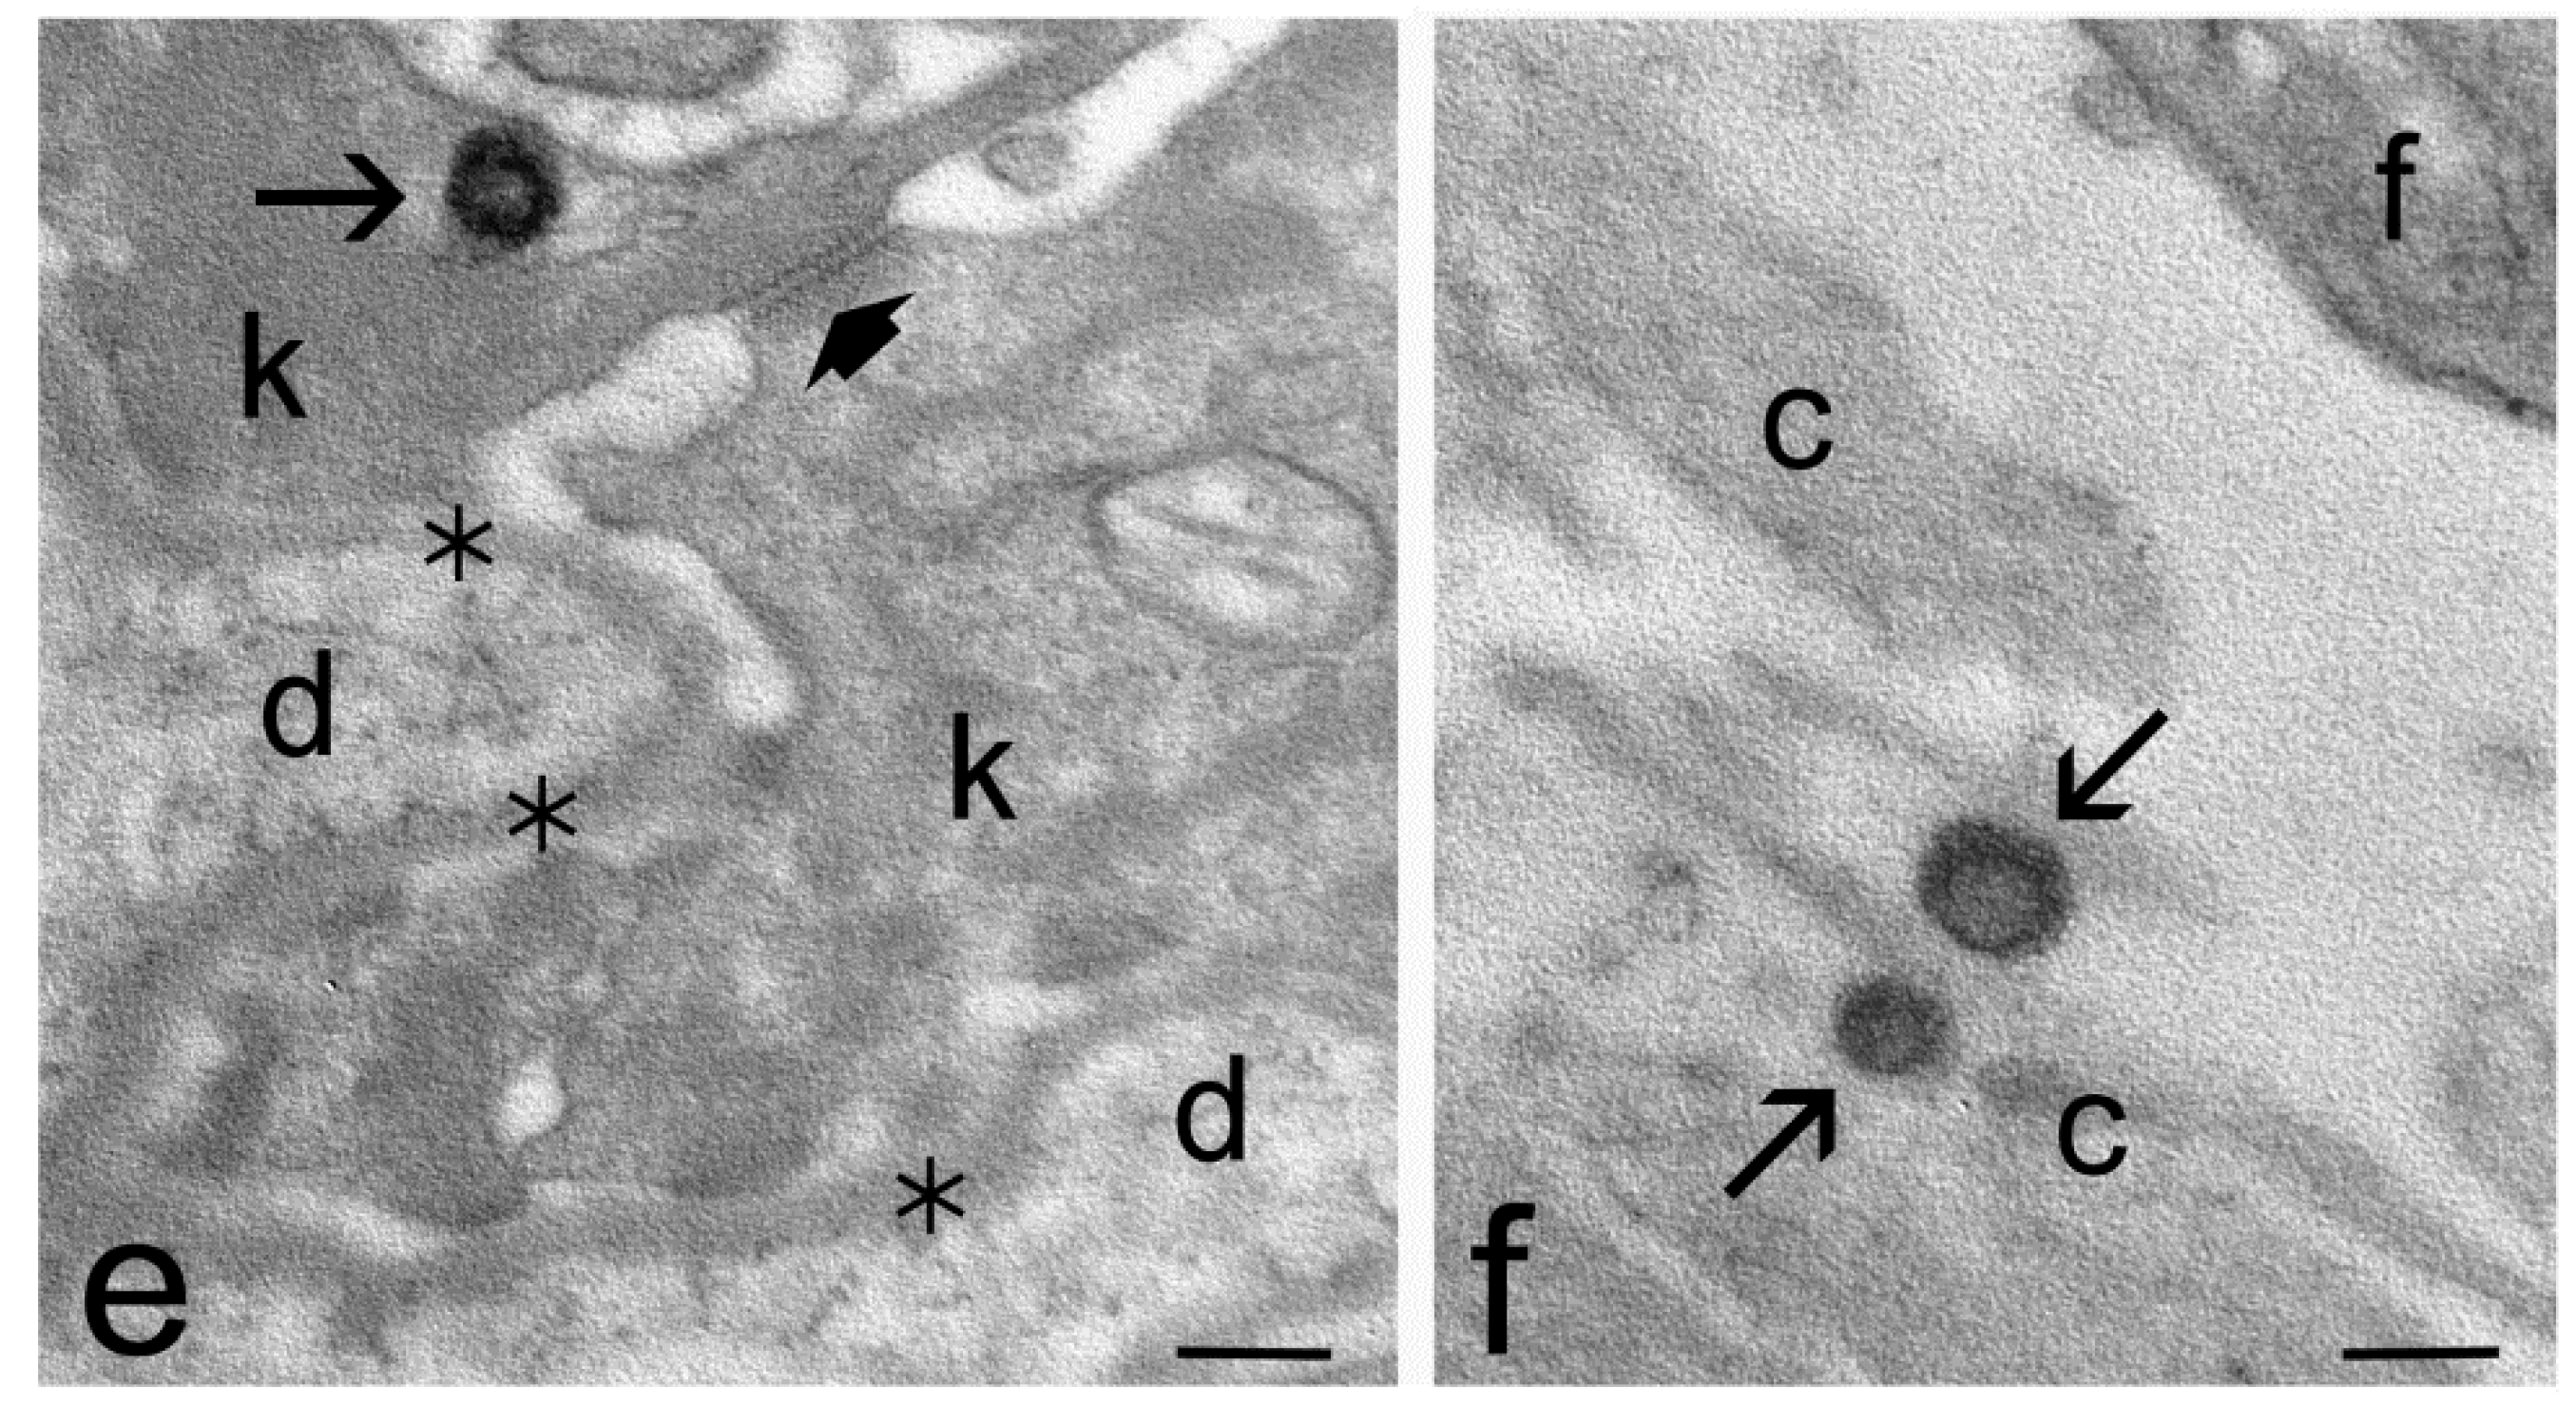

2.4. Transmission Electron Microscopy Study of Skin Penetration

| Skin Strata | ET | TET-1 | TET-2 |

| Stratum corneum | yes | yes | yes |

| Keratinocytes | yes | yes | no |

| Dermis | yes | no | no |